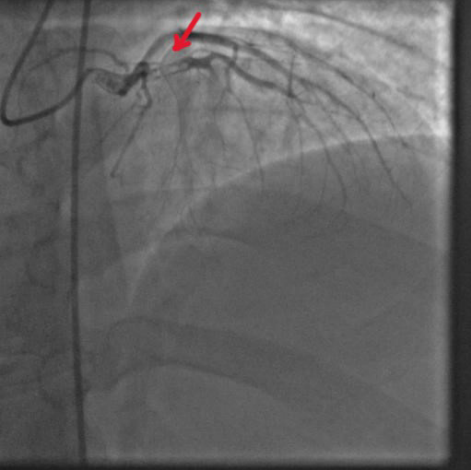

Повторно зарегистрирована ЭКГ — синусовый ритм, сохраняется элевация ST в отведениях I, aVL, V2-V6, реципрокные изменения в отведениях II, III, aVF. Из приемного покоя пациент был направлен в рентгеноперационную. На коронарографии: тип кровоснабжения правый, в передней межжелудочковой ветви (ПМЖВ) пристеночные тромбы в верхней трети, окклюзия за 1 диагональной артерией (ДА), кровоток TIMI 0-1, остальные артерии интактны, признаков коронарного атеросклероза не обнаружено (рис. 6-8). Попытки тромбоаспирации оказались без эффекта. В зону тромбоза в верхней трети ПМЖВ имплантирован стент. Многократные попытки баллонной ангиопластики ПМЖВ от развилки с 1 ДА до дистальных отделов без эффекта. Сохранялся кровоток по ПМЖВ ТIМІ — 0-1. В 1 ДА и дистальнее поочередно имплантированы 2 стента. Несмотря на все усилия и внутриартериальное введение изокета кровоток по ТIМI оставался на уровне 0-1. Появилась стагнация кровотока в дистальных отделах 1 ДА. Дальнейшее вмешательство было решено прекратить, и пациент был переведен в отделение реанимации.

Рис. 6. Тромбы в ПМЖВ.

Рис. 7. Тромботическая окклюзия за первой ДА.